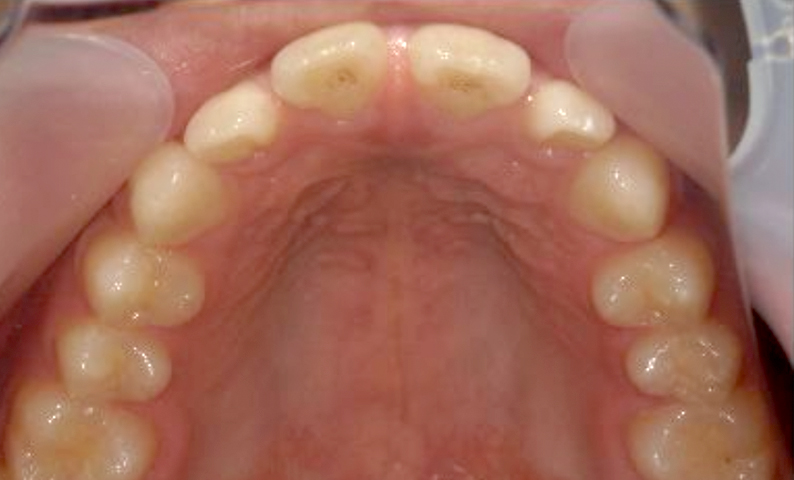

| 治療前 | 治療後 |

|---|---|

|